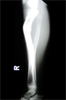

Intra

Op

Acute shortening held with wires